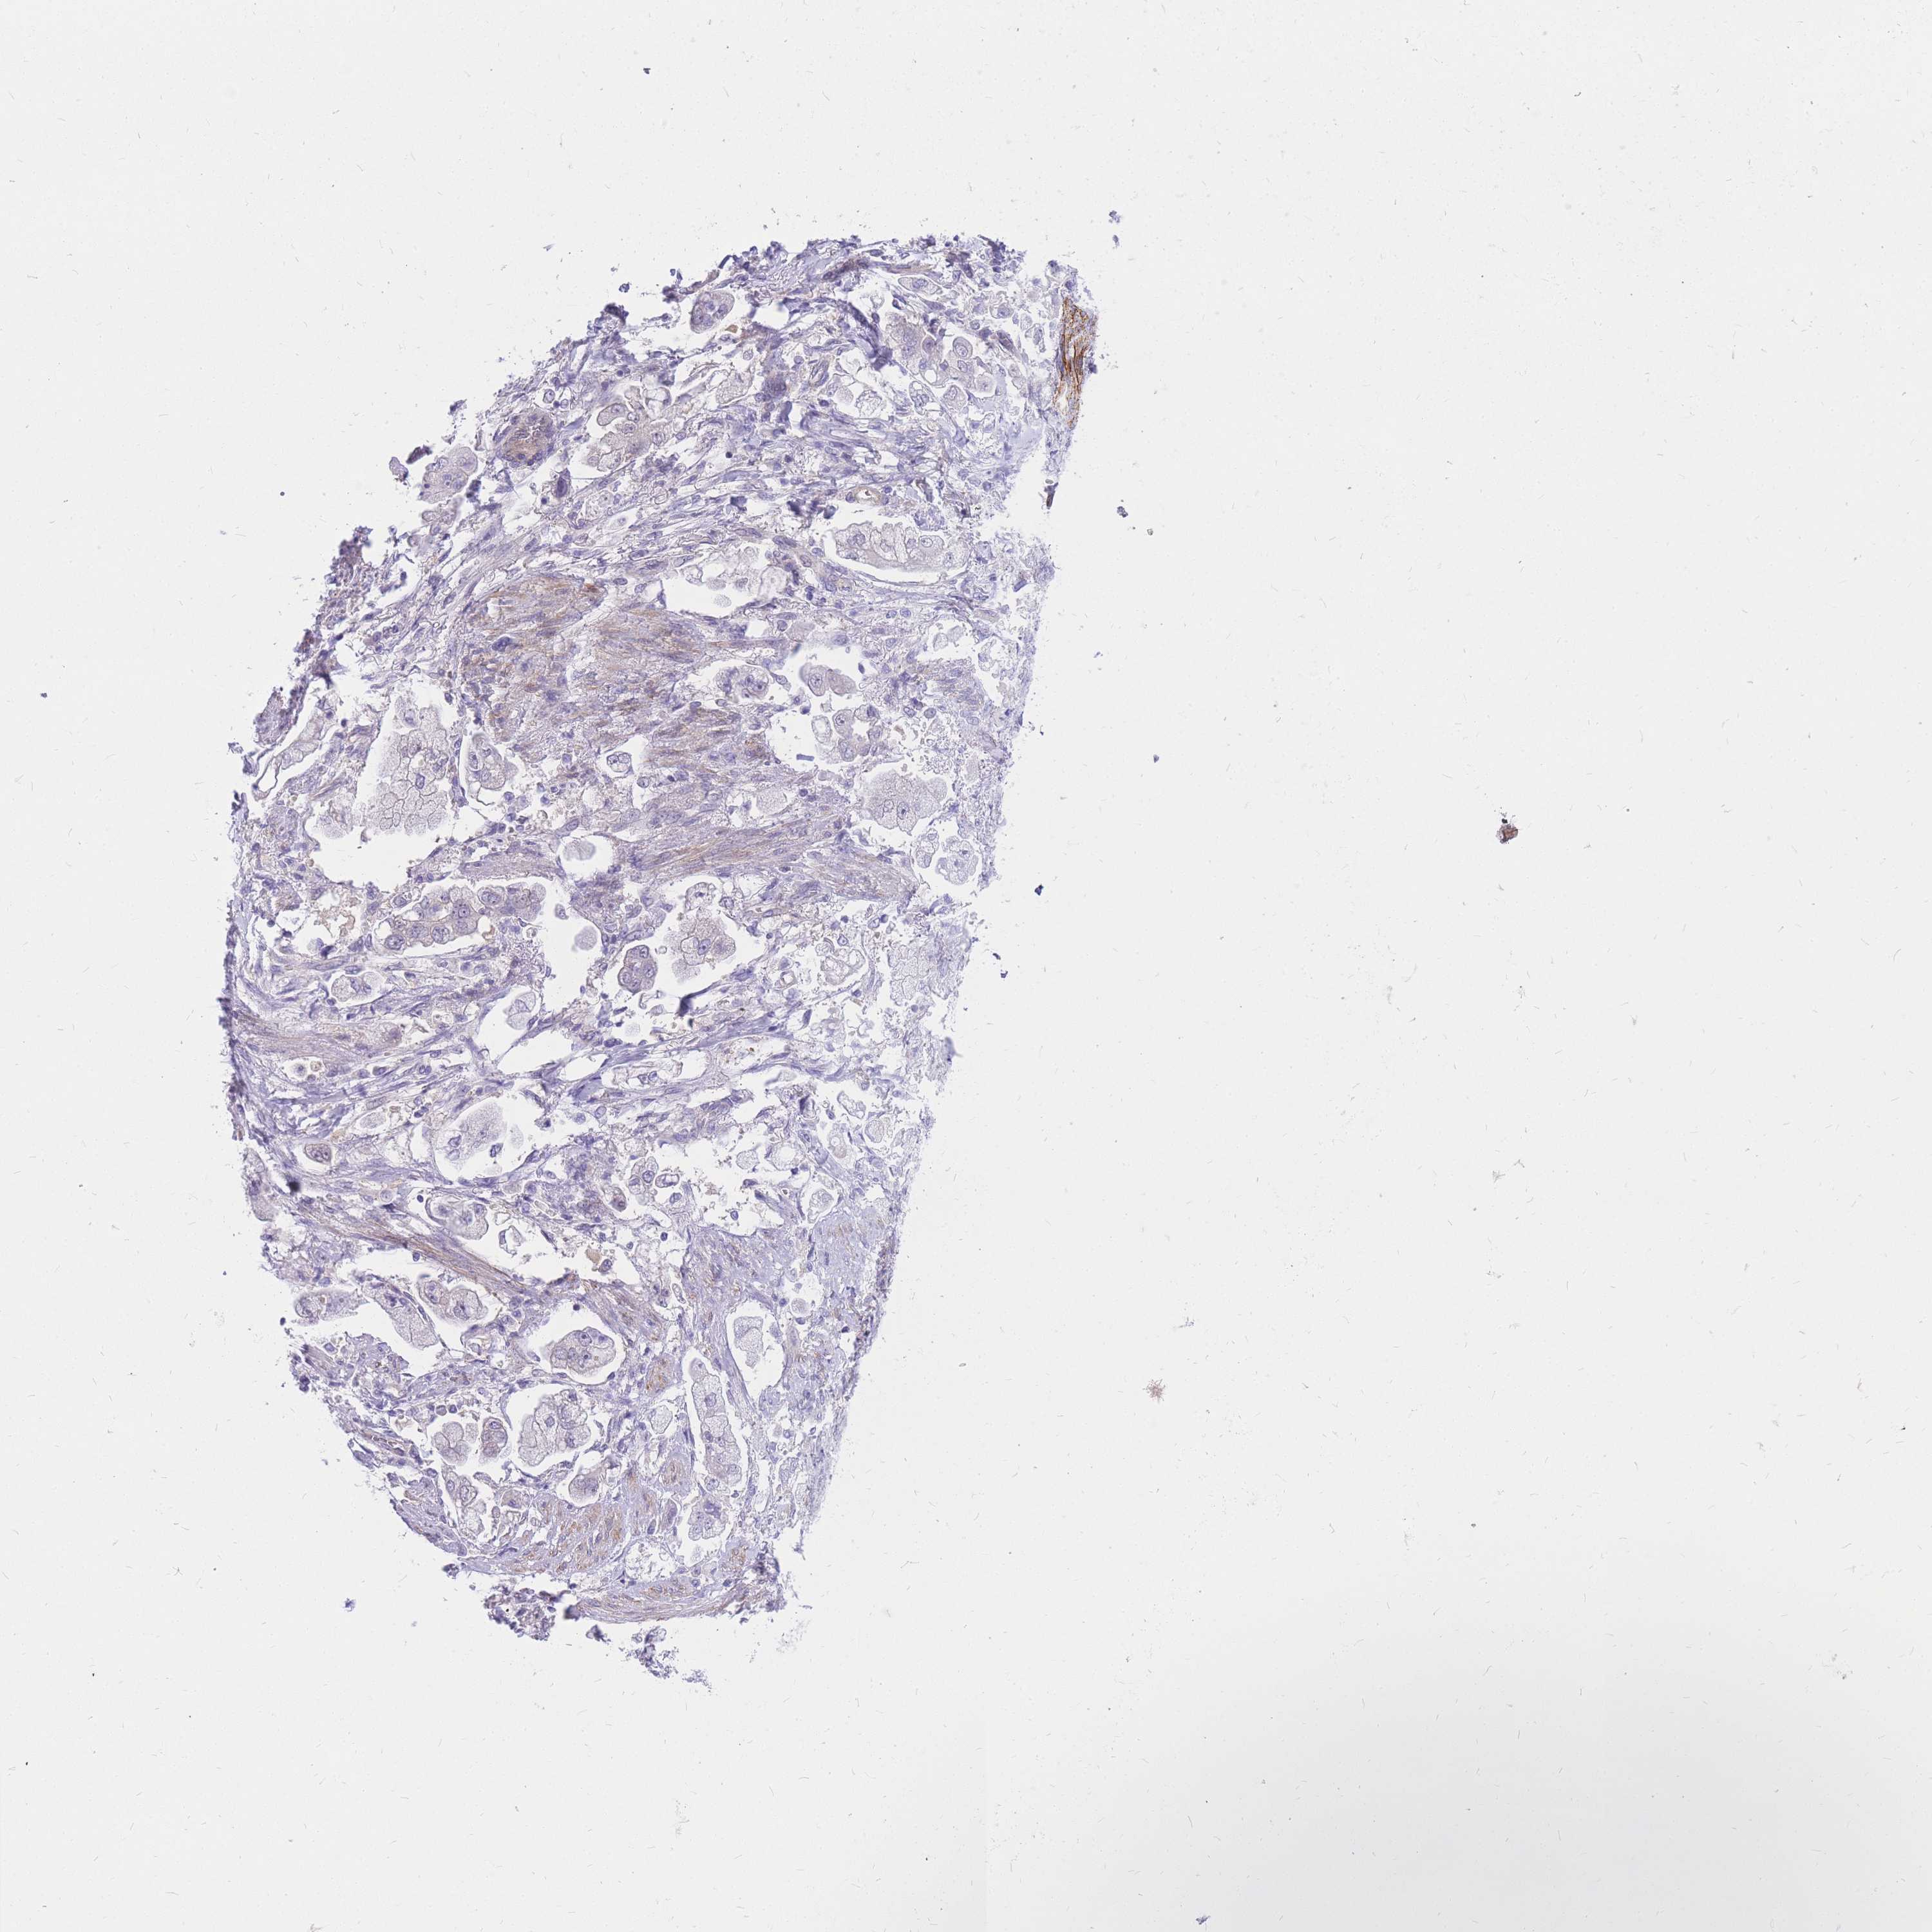

STOMACH CANCER - Protein expressioni

A mouse-over function shows sample information and annotation data. Click on an image to view it in a full screen mode. Samples can be filtered based on level of antibody staining by selecting one or several of the following categories: high, medium, low and not detected. The assay and annotation is described here.

Note that samples used for immunohistochemistry by the Human Protein Atlas do not correspond to samples in the TCGA dataset.

Antibody stainingi

Antibody staining in the annotated cell types in the current human tissue is reported as not detected, low, medium, or high, based on conventional immunohistochemistry profiling in selected tissues. This score is based on the combination of the staining intensity and fraction of stained cells.

Each image is clickable and will lead to virtual microscopy that enables deeper exploration of all samples and also displays staining intensity scores, fraction scores and subcellular localization as well as patient and tissue information for each sample.

Antibody HPA027242

Antibody HPA027328

Staining

High

Medium

Low

Not detected

Intensity

Strong

Moderate

Weak

Negative

Quantity

>75%

75%-25%

<25%

None

Location

Nuclear

Cytoplasmic/membranous

Cytoplasmic/membranous,nuclear

Adenocarcinoma, NOS